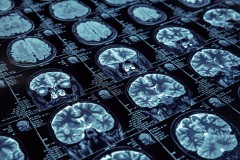

Przygotuj się do rezonansu magnetycznego

Wykonaj poniższe kroki, aby w pełni być gotowym do badania rezonansem.

Jak przygotować się do badania rezonansem magnetycznym? Podsumowanie

Badanie rezonansem magnetycznym może dostarczyć cennych informacji diagnostycznych i przyczynić się do postawienia trafnej diagnozy. Przygotowanie się do tego badania może pomóc w jego efektywnym przeprowadzeniu. Pamiętaj o skonsultowaniu się z lekarzem, usunięciu metalowych przedmiotów, odpowiednim ubiorze, zgłoszeniu obaw związanych z klaustrofobią, przygotowaniu się na długotrwałe badanie oraz zachowaniu spokoju i relaksu. Przestrzeganie instrukcji personelu medycznego jest kluczowe dla skutecznego i bezpiecznego przeprowadzenia badania rezonansem magnetycznym.